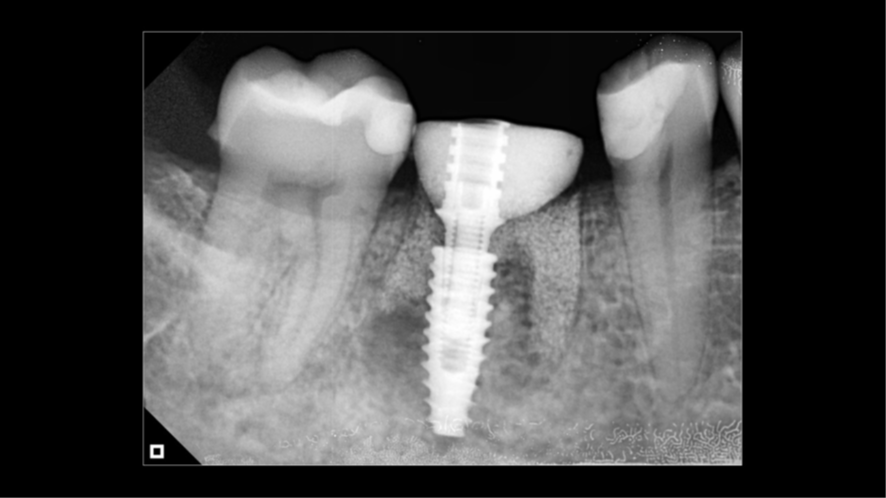

Agora, o laboratório de prótese consegue alinhar as malhas e fazendo a subtração da malha referente ao escaneamento do cicatrizador personalizado fora da boca, parafusado no análogo, temos exatamente o perfil de emergência adquirido pelo cicatrizador personalizado. Então, é realizado o CAD da coroa sobre implante (Figura 16), e após a fresagem em zircônia, acabamento, polimento e maquiagem, recebemos a coroa fresada em zircônia cimentada no pilar Base T (Figuras 17 e 18) pronta para ser instalada no implante. Logo após a instalação da coroa sobre implante (Figura 19), uma radiografia periapical foi realizada (Figura 20), a fim de confirmar a adaptação correta da coroa sobre implante.